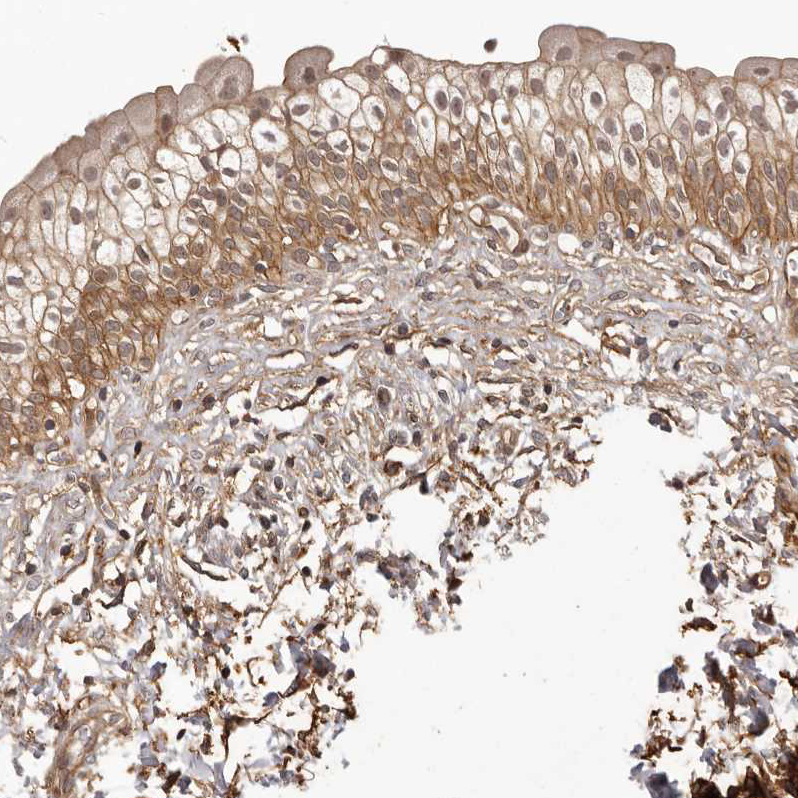

Immunohistochemical staining of human urinary bladder shows moderate membranous positivity in urothelial cells.